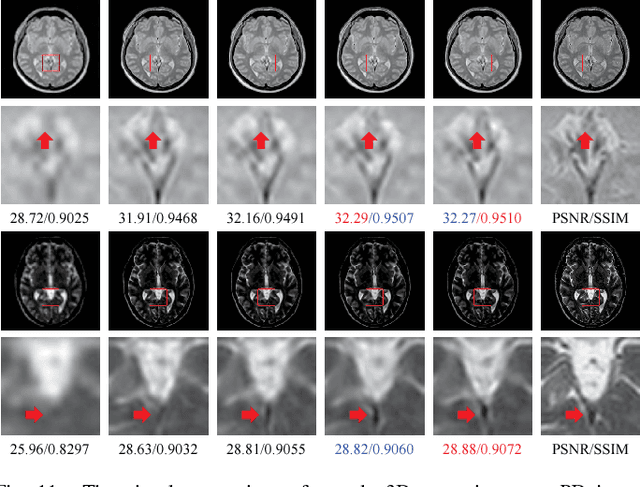

Abstract:Spatial resolution is a critical imaging parameter in magnetic resonance imaging (MRI). Acquiring high resolution MRI data usually takes long scanning time and would subject to motion artifacts due to hardware, physical, and physiological limitations. Single image super-resolution (SISR), especially that based on deep learning techniques, is an effective and promising alternative technique to improve the current spatial resolution of magnetic resonance (MR) images. However, the deeper network is more difficult to be effectively trained because the information is gradually weakened as the network deepens. This problem becomes more serious for medical images due to the degradation of training examples. In this paper, we present a novel channel splitting and serial fusion network (CSSFN) for single MR image super-resolution. Specifically, the proposed CSSFN network splits the hierarchical features into a series of subfeatures, which are then integrated together in a serial manner. Thus, the network becomes deeper and can deal with the subfeatures on different channels discriminatively. Besides, a dense global feature fusion (DGFF) is adopted to integrate the intermediate features, which further promotes the information flow in the network. Extensive experiments on several typical MR images show the superiority of our CSSFN model over other advanced SISR methods.

Abstract:High resolution magnetic resonance (MR) imaging is desirable in many clinical applications due to its contribution to more accurate subsequent analyses and early clinical diagnoses. Single image super resolution (SISR) is an effective and cost efficient alternative technique to improve the spatial resolution of MR images. In the past few years, SISR methods based on deep learning techniques, especially convolutional neural networks (CNNs), have achieved state-of-the-art performance on natural images. However, the information is gradually weakened and training becomes increasingly difficult as the network deepens. The problem is more serious for medical images because lacking high quality and effective training samples makes deep models prone to underfitting or overfitting. Nevertheless, many current models treat the hierarchical features on different channels equivalently, which is not helpful for the models to deal with the hierarchical features discriminatively and targetedly. To this end, we present a novel channel splitting network (CSN) to ease the representational burden of deep models. The proposed CSN model divides the hierarchical features into two branches, i.e., residual branch and dense branch, with different information transmissions. The residual branch is able to promote feature reuse, while the dense branch is beneficial to the exploration of new features. Besides, we also adopt the merge-and-run mapping to facilitate information integration between different branches. Extensive experiments on various MR images, including proton density (PD), T1 and T2 images, show that the proposed CSN model achieves superior performance over other state-of-the-art SISR methods.